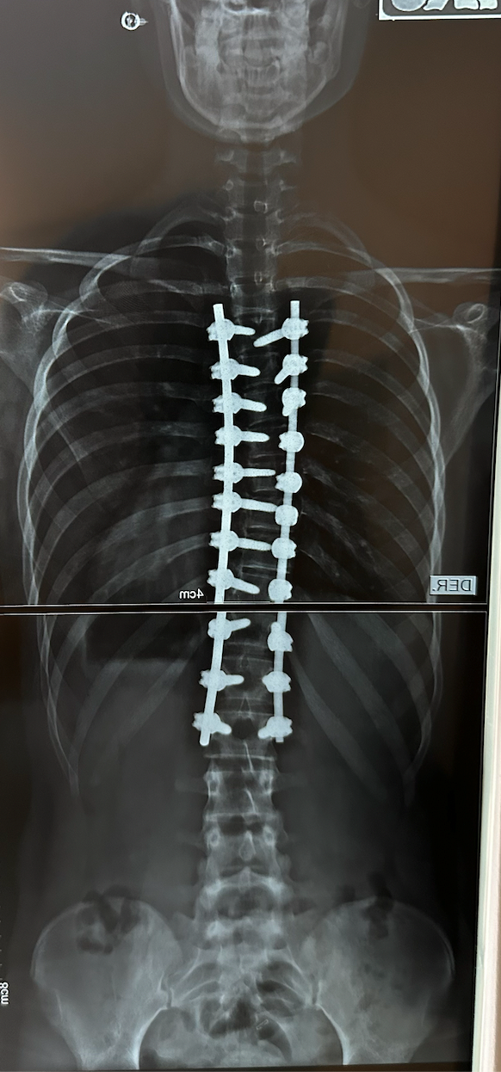

La operación se llevó a cabo el martes 7 de junio 2021 en el Sanatorio de Niños de Rosario, duró 6 horas y constó de la colocación de una barra de fijación de cobalto y 22 tornillos. El sábado 11 de junio ya recibíamos el alta. A las tres semanas volvió a la escuela, al mes andaba en bicicleta y a los 4 meses ya hacía vida normal nuevamente e hizo su viaje de séptimo realizando todas las actividades sin preocupaciones. Destacamos el profesionalismo, la calidad humana y el excelente trato del Dr. Pablo Fiorillo para con sus pacientes. Nos brindó mucha ayuda, nos transmitió la tranquilidad, siempre presente antes y después de la operación. No tenemos dudas que nuestra hija estuvo en las mejores manos.